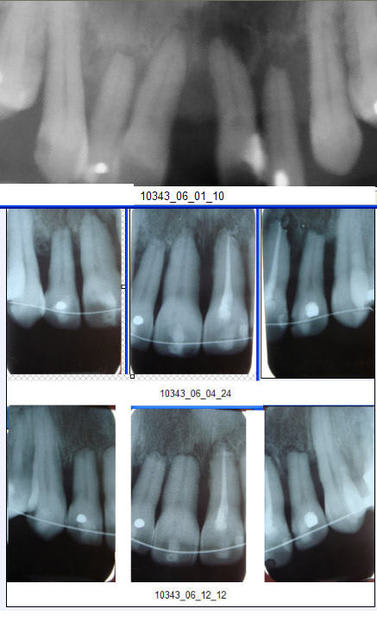

Encore un cas facile, mais sur adulte (43 ans)

Pour vous amuser !

P.S. Ici, on voit bien qu'un traitement radiculaire protège des résorptions radiculaires (une partie du pool cellulaire responsable des rhizalyses provient de la pulpe). Je regrette de l'avoir oublié et de ne avoir demandé d'en faire en préventif sur toutes les incisives.

10343 radios zfpiwb - Eugenol